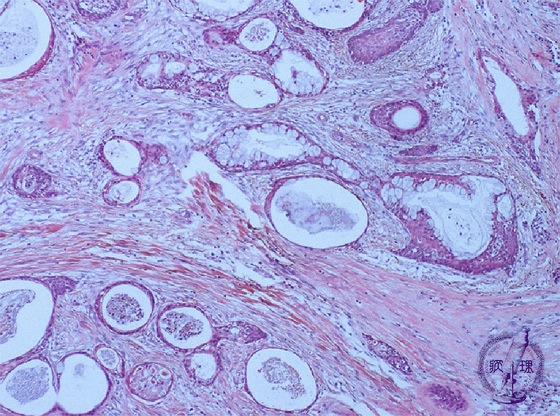

Microscopic finding (HE stain, low-power view):The tumor cells form abundant glandular or cystic nests (well differentiated).